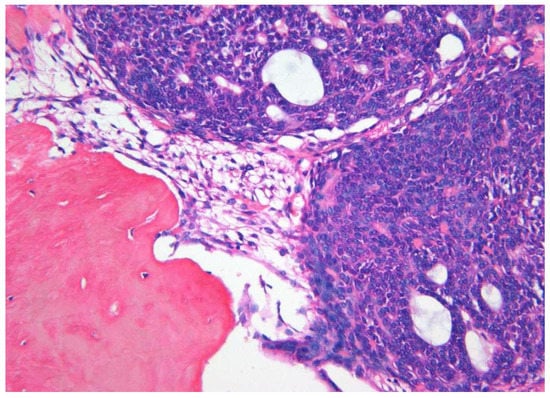

| Histopathology | ||||

| 1. Capsule-present | 10 (90.9) | 24 (80.0) | 34 | |

| 2. Epithelial component | ||||

| 2a. Duct like structures | 09 (81.8) | 27 (90.0) | 36 | |

| 2b. Epithelial whorls | 11 (100) | 29 (96.6) | 40 | p = 0.7 |

| 2c. Rosettes | 03 (27.2) | 19 (63.3) | 22 | |

| 2d. Trabeculae | 08 (72.8) | 25 (83.3) | 33 | |

| 3. Stromal component | ||||

| 3a. Tumour droplets | 08 (72.8) | 20 (66.6) | 28 | |

| 3b. Calcifications | 11 (100) | 29 (96.6) | 40 | p = 0.8 |

| 3c. Osteo-dentine | 01 (09.1) | 01 (03.3) | 02 | |